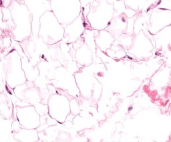

Adipose